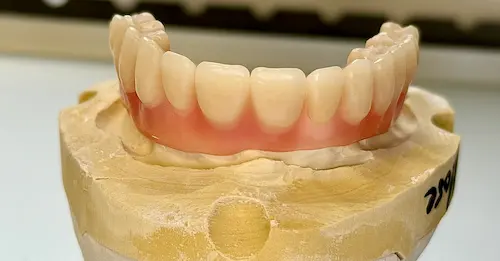

5. Nach ca. 4-6 Monaten: Abformung des Kiefers zur Herstellung Ihres endgültigen Zahnersatzes

6. Ca. 7-10 Tage später: Anprobe Ihres endgültigen Zahnersatzes

Der chirurgische Eingriff im Detail

Der Tag der Operation ist gekommen: Im ersten Schritt werden die noch vorhandenen Zähne gezogen sowie die Wurzeln und vereinzelte Zysten restlos entfernt. Dies erwies sich im vorliegenden Fall als extrem komplex und folgenreich: Beim Extrahieren gingen Teile der Knochenwände verloren, was einen deutlichen Mehraufwand beim Aufbau des Kieferkamms nach sich zog. Zuzüglich zu Knochenersatzmaterial verwendete Dr. Mintert dafür 2 Collagen Blöcke, 2 Membranen und 0,3 ml Emdogain. Letzteres dient der Entwicklung von zahnstützendem Gewebe. Auch Eigenknochen aus einem zweiten OP-Gebiet kam zum Einsatz. Im Oberkiefer wurde außerdem ein sogenannter Sinuslift durchgeführt, der – vereinfacht gesprochen – die Kieferhöhlen anheben soll. Nun waren die Grundlagen für den nächsten Schritt geschaffen: Eine eigens angefertigte Bohrschablone ermöglicht die navigierte Implantation. So fanden alle acht Implantate trotz ungeplanter Komplikationen ihren rechten Platz im Mundraum. Abschließend wird L-PRF Plasma, d.h. zentrifugiertes Eigenblut eingebracht, um die Wundheilung zu unterstützen. Als Zahnersatz werden zwei festsitzende Keramikbrücken gewählt und auf künstliche Keramikaufbauten geklebt. Diese wiederum sind mit jeweils vier Implantaten verschraubt.

All-on-Four Zahnersatz nach OP - Patientenansicht